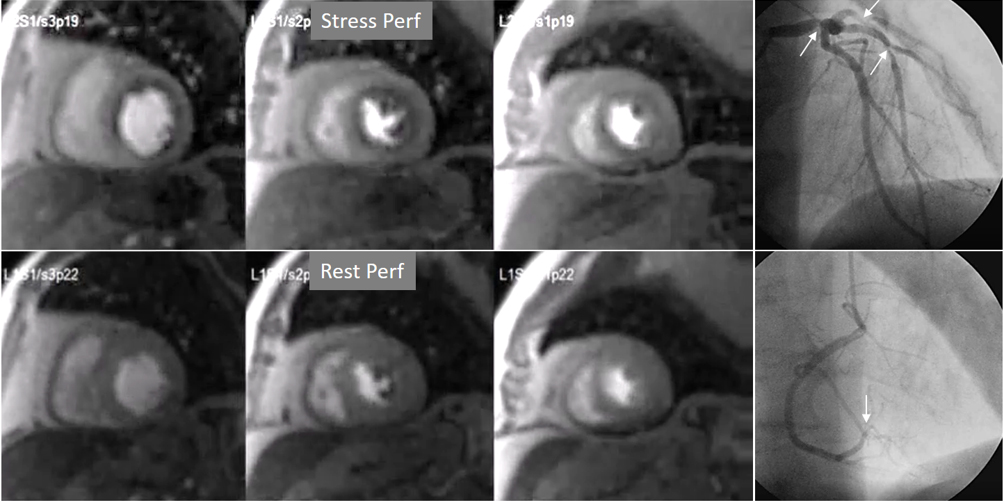

Perfusion defects in different territories can be detected in case of multivessel disease (Fig. 7) and, in patients with severe 3-vessel CAD, the perfusion study may show a global, intense, persistent defect which is readily recognizable (Fig. 8).

Fig. 7.Two-vessel perfusion defect. Stress perfusion defects at the anterior (white arrows) and inferior (black arrows) walls, not present at rest. Angiography (right panels) shows significant stenoses (white arrows) of the LAD (upper panel) and the right coronary artery (RCA) (lower panel).

Fig. 8.Three-vessel perfusion defect. Stress and rest studies in a patient with severe left main and 3-vessel CAD (arrows, on the right panels) showing an inducible perfusion defect in most, if not all, of the myocardial segments during vasodilatory stress.